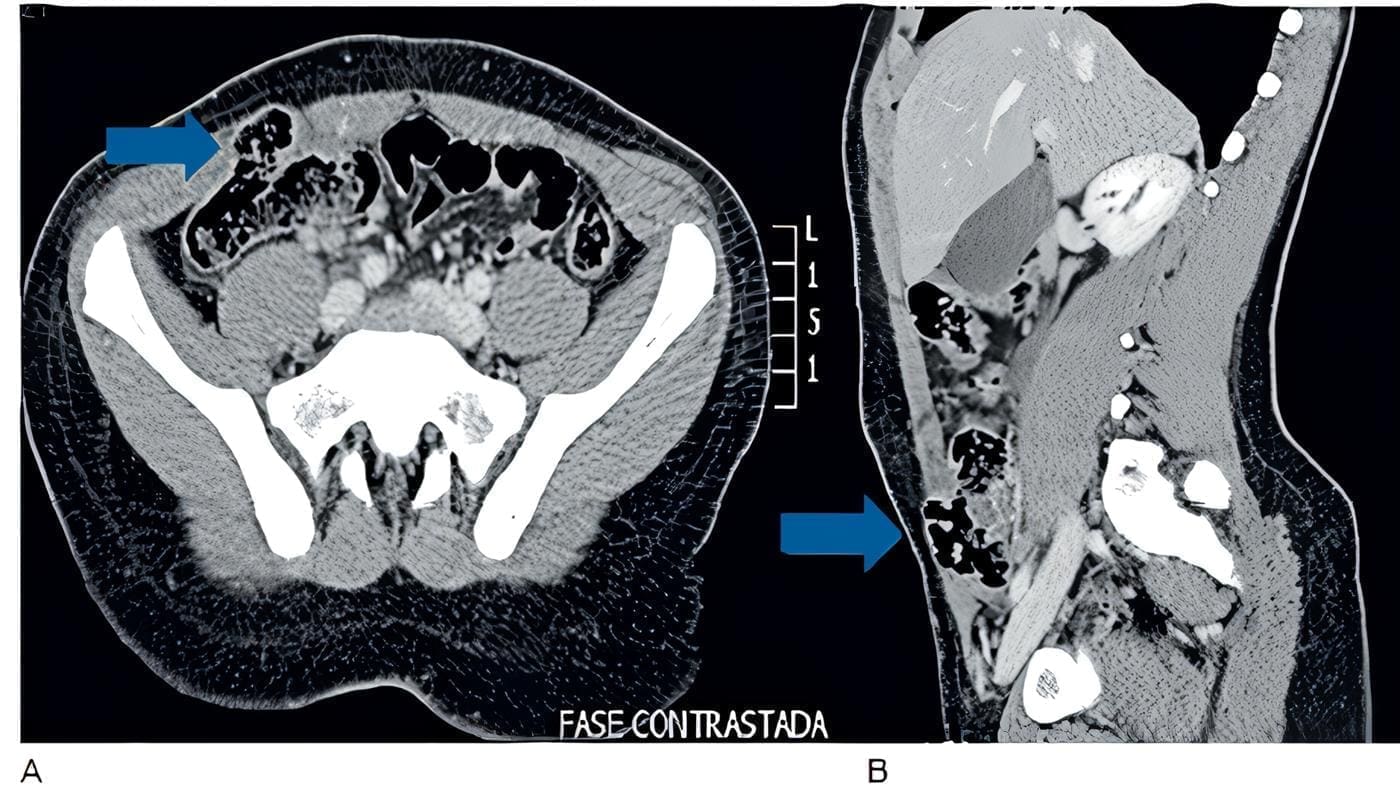

Realizan tomografía computarizada (TC) de abdomen que muestra escaso líquido libre en el fondo de saco derecho y lo que consideraron una “hernia de Spiegel” (Figura 2).

Figura 2. Tomografía abdominal en corte axial (A) y sagital (B) que diagnostica la hernia traumática

de la pared abdominal. Las flechas indican el punto del defecto de la pared abdominal con

herniación visceral. Fuente: servicio de radiología del hospital Pablo Tobón Uribe, Medellín, Colombia.

Por la relación con el trauma y la ausencia de hernia previa, se hizo diagnóstico de hernia traumática y se llevó a cirugía donde se encontró un gran defecto de la pared abdominal.